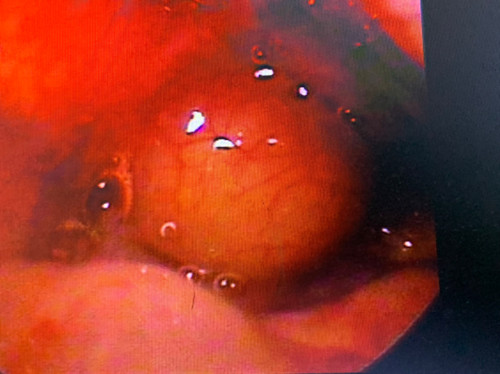

相关检查:间接喉镜、显微或电子喉镜检查,可发现位于会厌部位的类圆形或半球形肿物,表面光滑,蒂部广,可呈灰白、浅黄或淡红色。

低温等离子切除术后2天复查